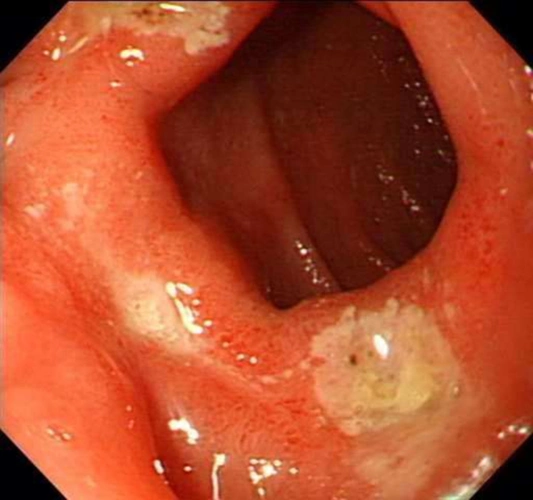

反酸,干呕,打嗝,可能是胃溃疡,中医根治用1个食疗方子